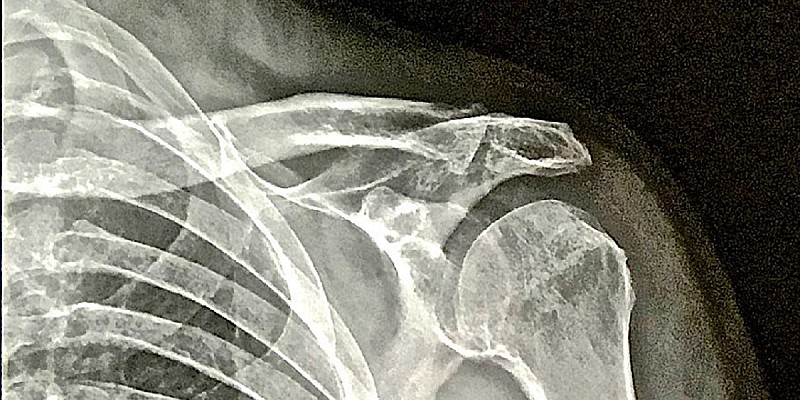

Se il trattamento conservativo prevede l’immobilizzazione in tutore della spalla per un periodo di 2-3 settimane ed il successivo percorso riabilitativo, il trattamento chirurgico considera molteplici opzioni, artroscopiche o a cielo aperto, sia di stabilizzazione capsulo-legamentosa (Intervento di Bankart ed eventuale Remplissage) che di augmentation osseo (Bone Block, Latarjet) in base al tipo di lesione diagnosticata nello studio pre-operatorio (Fig. 1) ed ai fattori di rischio considerati.

Fig. 1: Immagine Tc di paziente con lesione bony bankart dopo primo episodio di instabilità anteriore post traumatica in paziente maschio di anni 20, sportivo